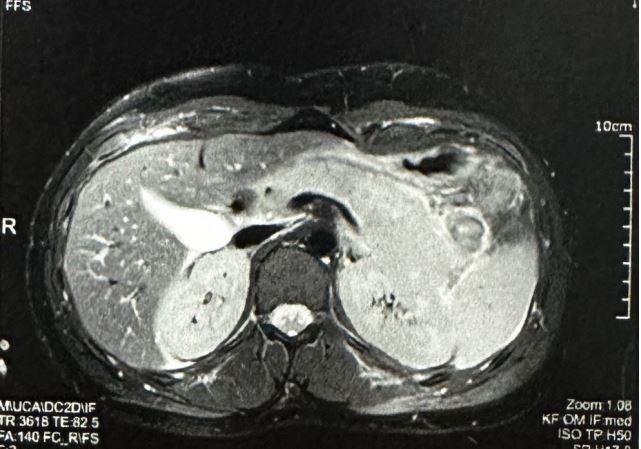

A Moroccan 17 year old male presented to the emergency department for four days of newly experienced epigastric pain associated to non-bloody and non-bilious emesis. The patient the child was diagnosed with epilepsy for which treatment with sodium valproate was initiated. The last dosage is changed nine months before from 750 mg to 1 g to maintain a dose of 20 mg/kg/d. There was no seizure the last year. On presentation he denied history of other new medications, supplements, alcohol or drug use, gallstones, fevers or chills. The epigastric pain was intense and resistant to anttispasmodic and oméprazole. Physical examination on arrival was notable for uncomfortable appearing, he complains of intense localized pain in the epigastrium radiating towards the back with an attitude of leaning forward. He was apyretic. On palpation we noted a focal epigastric tenderness with non-peritonitic abdomen. Respiratory and hemodynamic functions were stable. blood pressure 125/67, pulse 87, respiratory rate of 20, spo2 of 100%. The rest of the physical examination findings were unremarkable without any rashes, joint swelling, or adenopathy. Serum laboratory investigations in the emergency department revealed the following pertinent and significant findings: lipase level of 462 U/l, white blood cell count of 11.000 per mm3 , Activated protein C 27 mg/l, hemoglobin 10.6 g/dl, AST 28U/L, ALT 25U/L, Total bilirubin 8.2 mg/L, sodium 141 mmol/l, potassium 4.2 mmol/l, BUN 0.35 g/l, creatinine 10,2 mg/l, calcium 90 mg/l, and. All other initial laboratory invetigations within normal limits or insignificant. Patient was resuscitated with two liters of isotonic saline serum, received a total of 40 mg of intravenous omeprazole, 500 mg of intravenous paracetamol, and 4 mg of intravenous morphine. Initial abdominal ultrasound showed a normal gallbluddder, without any stones, gallbludder wall thickening, or common bile duct dilatation. the pancreas is globular with infiltration of gastric fat and presence of moderate peritoneal effusion (Figure 1). Subsequently, patient underwent a computed tomography of abdomen and pelvis with intravenous contrast (Figure 2). The pancreas was enlarged, had a homogeneous density, with a discreet homogeneous enhancement without an area of pancreatic parenchymal necrosis. presence of a peritoneal effusion of medium abundance surrounding the pancreas, perigastric, perihepatic, perisplenic level and in pelvic slope. The gallbladder, bile ducts, liver, spleen and kidneys were without abnormalities. The appearance was an acute edematous pancreatitis grade E of Balthazar. Patient was admitted to intensive care unit, he continued to receive intravenous boluses and maintenance fluids per standards of care for acute pancreatitis, along with adjunct therapies including antispasmodic, omeprazole and morphine to control pain. Food is reintroduced gradually from the 3rd day after the nausea and vomiting have disappeared and the pain has been controlled. we started with water, herbal teas, vegetable broths in small volumes. All this while monitoring digestive tolerance and the absence of pain. During the first days of hospitalization, patient underwent an extensive panel of investigations including bili-MRI showed the absence of stones in the Wirsung duct and bile ducts which are not dilated, no malformation or pancreatic mass is revealed (Figure 3). The other investigations were hematological toxicology screen, viral screening (including A, B and C hepatitis panel, respiratory viral panel, measles mumps rubella panel Epstein barr, cytomegalovirus panel), TPHA VDRL serology, tuberculosis quantiferon, lipid panel (cholesterol 1.46 g/L, triglycerids 0.9 g/L), blood smear, thyroid panel, antinuclear and anticardiolipin antibodies, hemoglobin electrophoresis; all returning either within normal or unremarkable limits. The absence of another cause responsible for pancreatitis led us to consider the drug etiology, particularly sodium valproate. Neurology consult was placed. Treatment with valproate of sodium was stopped and replaced by levetiracetam 250 mg twice a day. The opatient made a full recovery and was discharged after a total of eight days with prescription of levetiracetam. Any epileptic crisis was observed. The patient continue to have regular outpatient neurology follow up.

Figure 2: Abdominal and pelvic computed tomography showing acute edematous pancreatitis Class E of Balthazar.